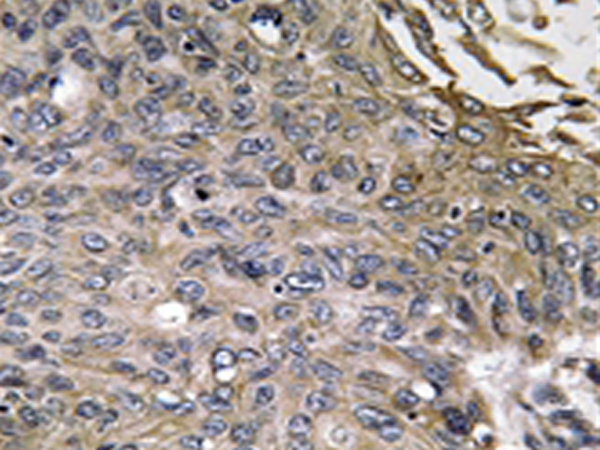

IHC positive control: |

Human lung carcinoma tissue |

IHC Recommend dilution: |

50-100 |